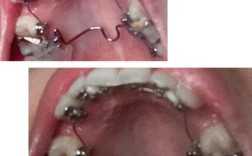

金属托槽矫正器:

(图片来源网络,侵删)- 原理: 在牙齿表面粘贴金属托槽,用金属丝(弓丝)穿过托槽结扎固定,通过弓丝的弹性力量移动牙齿。